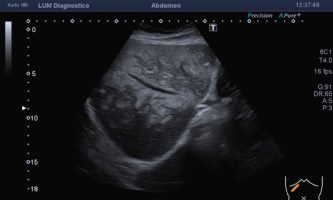

El médico de referencia le indica nueva ecografía de control, donde se observan múltiples y extensas lesiones focales hepáticas hiperecogénicas, redondeadas y confluentes, las cuales predominan en adyacencia a venas supra hepáticas, sin condicionar efecto de masa y sin alteración de la superficie hepática(fig. 1 y 2). Ante la valoración con Doppler color no presenta patrón de flujo peri ni intralesional y respeta el calibre de las venas supra hepáticas(fig. 3 y 4). Dada las características ecográficas se sospecha esteatosis focal multinodular confluente como principal diagnóstico presuntivo, siendo los diagnósticos diferenciales patologías de naturaleza infecciosa, tumoral o metastásica.